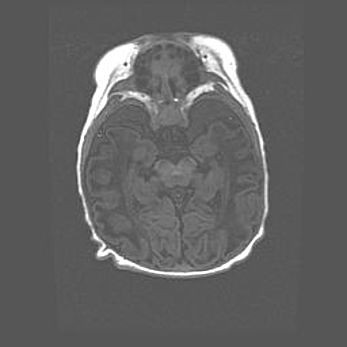

Лейкомаляция с кистозно-глиозной дегенерацией головного мозга.

Возраст: 2 месяца 25 дней

Вес: 6400 г

Окружность головы: 40 см

Срок гестации: 41 неделя

Лейкомаляцию относят к ишемически-гипоксическим повреждениям головного мозга, диагностируемым у новорожденных. При лейкомаляции в головном мозге обнаруживают очаги некроза, возникшие после тяжелой гипоксии и нарушения кровотока. В процессе морфогенеза очаги проходят три стадии: 1) развития некроза, 2) резорбции и 3) формирования глиозного рубца или кисты. Перивентрикулярная лейкомаляция (ПЛ) встречается примерно в 12% случаев среди новорожденных, обычно – у недоношенных детей, причем, частота ее зависит от массы, с которой младенец появился на свет. Наибольшее число малышей страдает лейкомаляцией, если масса при рождении 1500-2500 г.